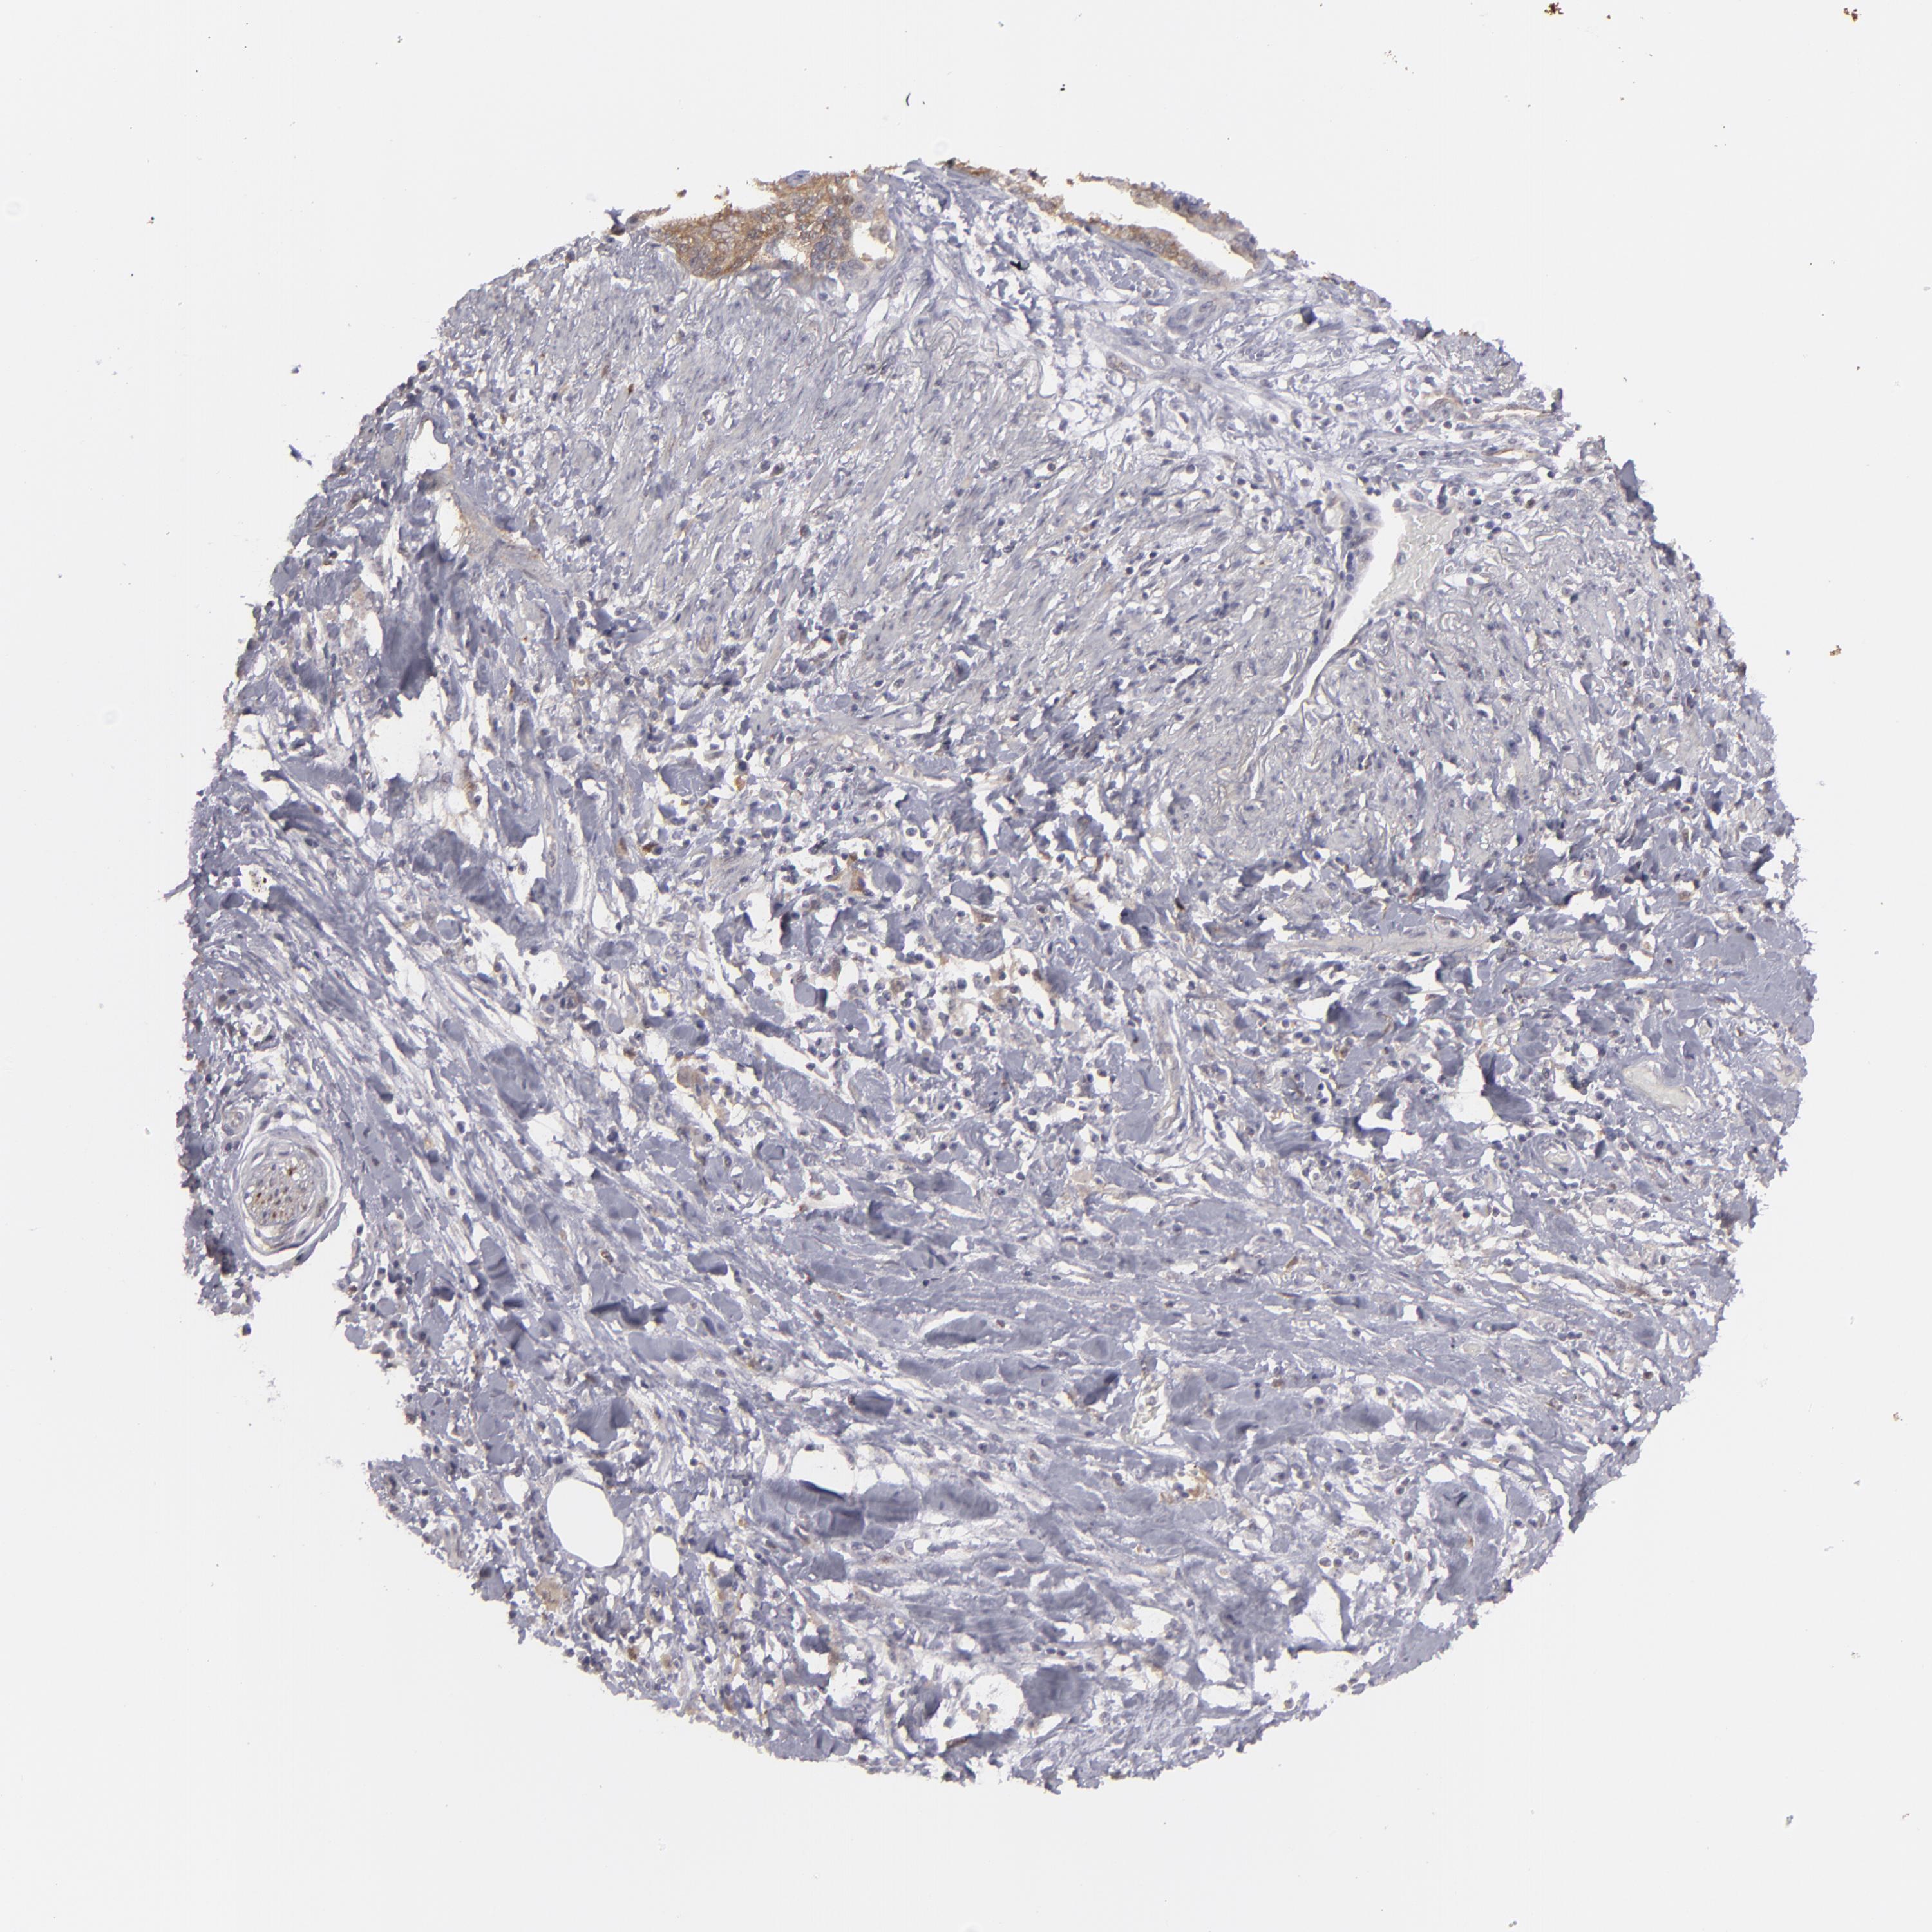

PANCREATIC CANCER - Protein expressioni

A mouse-over function shows sample information and annotation data. Click on an image to view it in a full screen mode. Samples can be filtered based on level of antibody staining by selecting one or several of the following categories: high, medium, low and not detected. The assay and annotation is described here.

Note that samples used for immunohistochemistry by the Human Protein Atlas do not correspond to samples in the TCGA dataset.

Antibody stainingi

Antibody staining in the annotated cell types in the current human tissue is reported as not detected, low, medium, or high, based on conventional immunohistochemistry profiling in selected tissues. This score is based on the combination of the staining intensity and fraction of stained cells.

Each image is clickable and will lead to virtual microscopy that enables deeper exploration of all samples and also displays staining intensity scores, fraction scores and subcellular localization as well as patient and tissue information for each sample.

Antibody HPA001761

Staining

High

Medium

Low

Not detected

Intensity

Strong

Moderate

Weak

Negative

Quantity

>75%

75%-25%

<25%

None

Location

Nuclear

Cytoplasmic/membranous

Cytoplasmic/membranous,nuclear

Adenocarcinoma, NOS